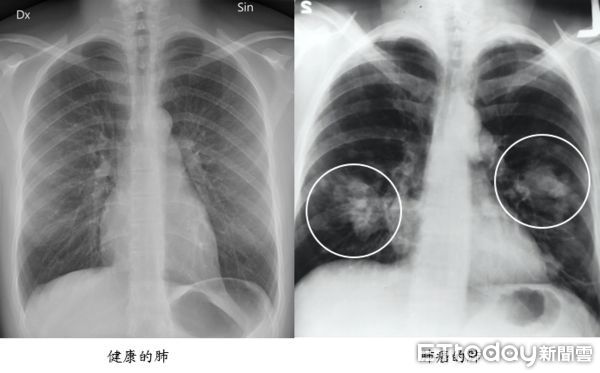

吸菸已被證實會增加癌症、腦中風、心肌梗塞、高血壓、慢性阻塞性肺病、消化性潰瘍等疾病的發生機率,二手菸、三手菸也會危害到家人及身邊人的健康。

台北榮總家庭醫學部林明慧主任表示,研究已證實,與吸菸者同住,得到肺癌的機會將比一般民眾高出20%-30%,二手菸暴露也會增加罹患冠狀動脈心臟病及罹病死亡風險;菸害也會造成或加重幼童氣喘、支氣管炎、肺炎、中耳炎的發生機會。